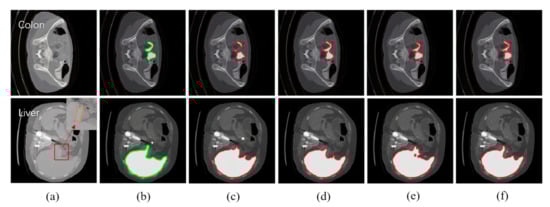

| Null | Null | Colon | SST | - | |||

| Our Algorithm | SST | ||||||

| Layer-freezing | |||||||

| Null | Null | Liver | SST | - | |||